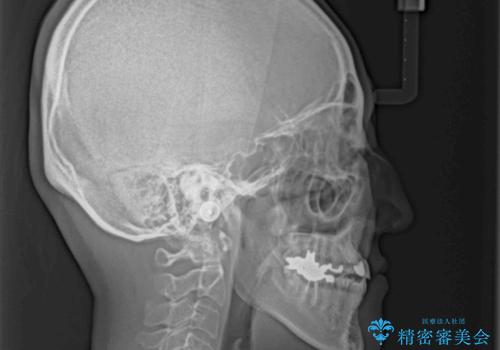

急速拡大装置 前歯の反対咬合をインビザラインで改善

- 前歯の反対咬合を気にして来院された患者様です。

上顎骨の幅が下顎骨よりも小さいので、拡大装置により骨幅を広げて上下関係を改善すると同時にワイヤー矯正で反対咬合の改善を図り、その後インビザラインにて歯並びを整えることとしました。

急速拡大装置の使用により奥歯の咬み合わせが劇的に変わり、その変化を利用して反対咬合を改善することができました。

治療期間中は奥歯が咬み合わず、食事が取りにくいなどの不都合がありましたが、最終的にはきれいに整えることができました。